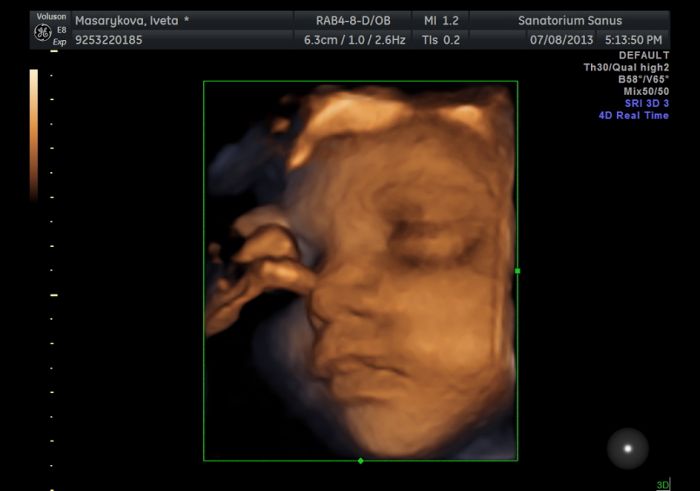

Ahojda...tak včerejší 3D UZ byl super Samík krasně spolupracoval až později po 6 kratých krasných videii se otočil na druhý bok že si dá šlofíka tak jsme to vzdali

mame i par foteček tak jestli se mi to povede tak vam toho našeho fešáka ukažu

[337853] jupíí povedlo se

prej ma pusinku po mě